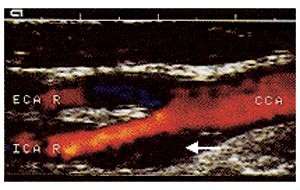

Forskjellige måter å klassifisere plakkekkogenisitet på er i bruk, og begrepsbruken er til dels forvirrende. Mange klassifiserer plakkekkogenisitet i fire kategorier (i engelsk litteratur kalt echolucent, predominantly echolucent, predominantly echogenic og echogenic) (5, 7) – (9), hvor kategori 1 er plakk med ren lavekkogen struktur (fig 1) og kategori 4 er plakk med høyekkogen struktur (fig 2). Noen bruker tre kategorier og andre benevnelser (10) – (12). Andre klassifiserer plakk som heterogene eller homogene, hvor heterogen brukes for å beskrive plakk av blandet ekkogenisitet med varierende innhold av lavekkogene soner, mens begrepet homogen beskriver plakk med middels eller høy plakkekkogenisitet (13, 14). Imidlertid kan begrepet homogent også brukes for å beskrive et plakk med jevn ekkostruktur, dvs. at et homogent plakk kan være både lavekkogent og høyekkogent (5, 10).

Ferske, uorganiserte tromber er lavekkogene strukturer som kan være vanskelige å skille fra lipidrike plakk. De mangler imidlertid fibrøs kapsel. Fargedoppler brukes til å skille et lavekkogent plakk eller en trombe fra karlumen.